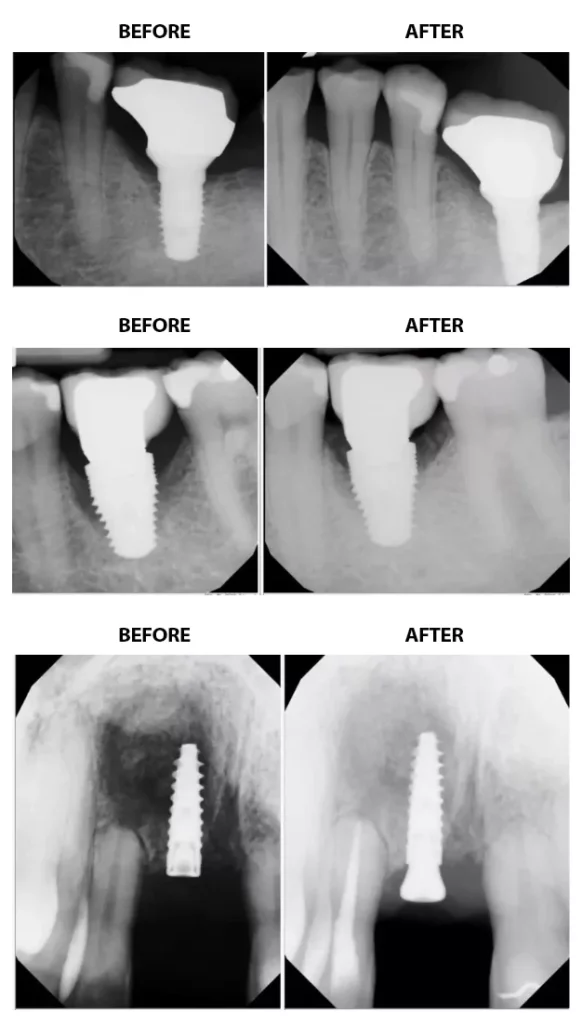

By incorporating laser-assisted dental implant repair into their treatment protocols, North Raleigh Periodontics and Implant Center can effectively address implant failure and help patients regain optimal oral health and function. This cutting-edge approach offers numerous benefits, including reduced discomfort during treatment, accelerated healing times, and enhancing long-term outcomes for patients facing implant complications. Through meticulous assessment and diagnostics, including thorough examination of clinical symptoms and radiographic imaging, the skilled team at North Raleigh Periodontics and Implant Center can determine whether laser-assisted regeneration technology is needed to repair a failing dental implant, or if more conservative measures are appropriate.